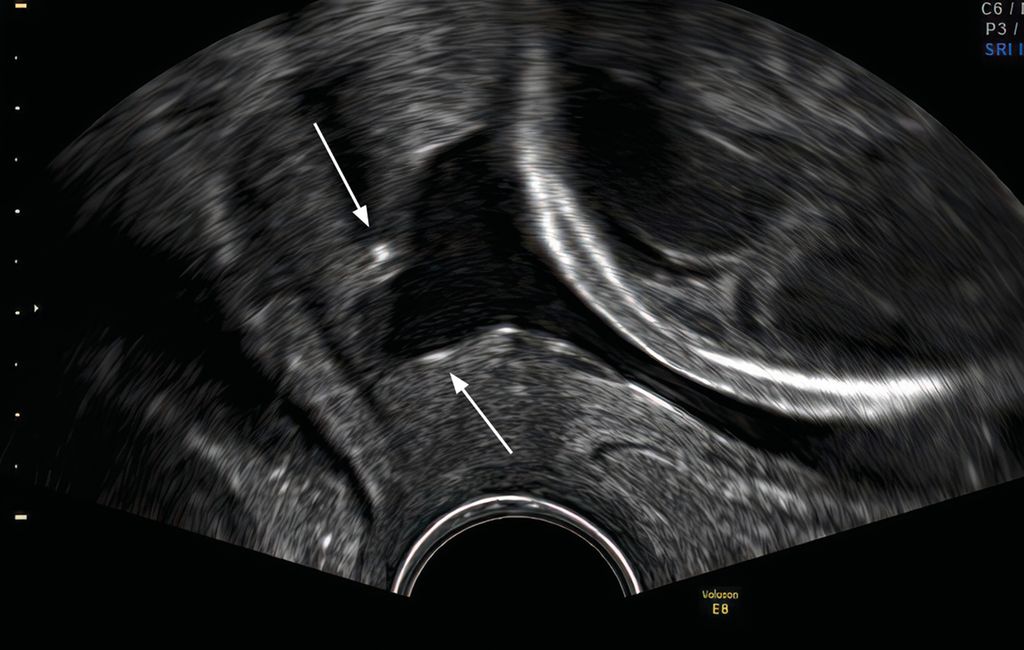

Zervixpessar

Eine Zervixinsuffizienz kann zu einem mechanischen Versagen des Gebärmutterhalses führen. Es gibt mehrere Hypothesen darüber, wie das Arabinpessar zur Vorbeugung von Frühgeburten beitragen könnte. Das Arabinpessar umschliesst den Gebärmutterhals, und verändert den Neigungswinkel des Zervikalkanals im Verhältnis zum Corpus uteri und reduziert den direkten Druck auf die Eihäute auf Höhe des inneren Muttermundes und auf den Muttermund (Abb. 2 und 3). Eine weitere Hypothese lautet, dass das Pessar den Zervixschleimpfropf schützt. Dies könnte dadurch erreicht werden, dass das Pessar die Anhaftung des verbleibenden Zervixgewebes unterstützt.19